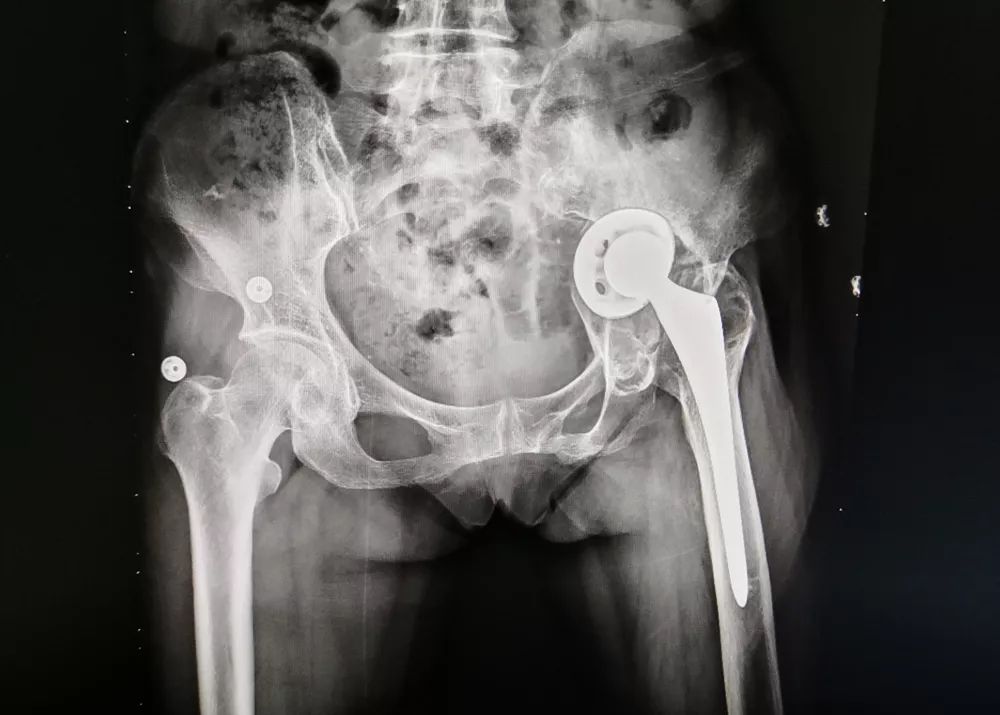

手术前

经详细检查后,该科医生发现,患者第一次手术已逾10年,两年来由于无法正常负重行走,患者已经出现重度骨质疏松、局部骨质溶解且严重变形、人工髋关节假体松动严重移位等情况。同时,由于患者第一次手术资料严重缺失,人工假体取出非常困难,现有传统内固定物也无法修复髋臼形状及提供髋臼负重能力。患者病情复杂,要实施手术难度极高,并发症多且严重,如:术中大出血、术中术后并发骨折、术后感染、下肢静脉血栓形成等。

2009年,家住在电白区的程奶奶因意外事故摔伤,导致左侧股骨颈骨折,受伤后在外地医院接受了“左侧人工全髋关节置换术”。约两年前,程奶奶开始感觉左髋部疼痛、活动受限,并且逐渐无法站立及行走。她曾多方求医,均未见效,日常生活与出行只能坐在轮椅上。为此,程奶奶内心异常焦灼,茶饭不思,人也逐渐消瘦。家属不甘心就这样放弃,后经人介绍,带程奶奶来到茂名市中医院骨三科进行治疗。